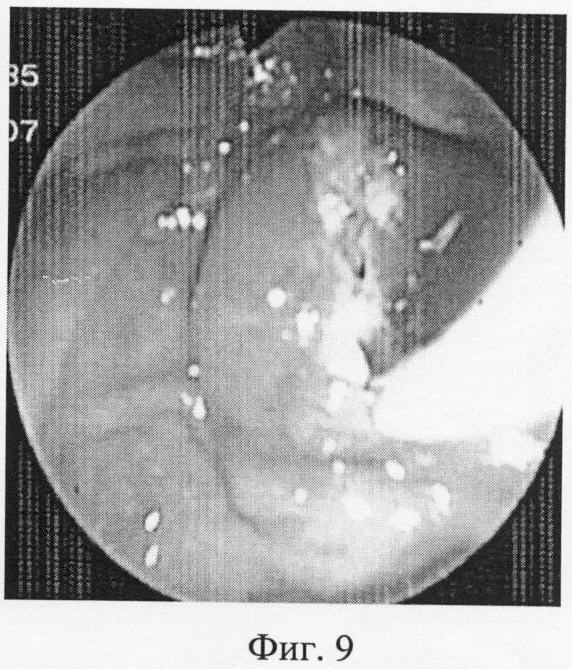

На эндоскопических фотографиях (фиг.6-12) наглядно представлены этапы операции эндоскопической папиллотомии предложенным новым нетипичным способом – крестообразным разрезом.

Фиг.9 – выполняется продольный разрез БСДК.